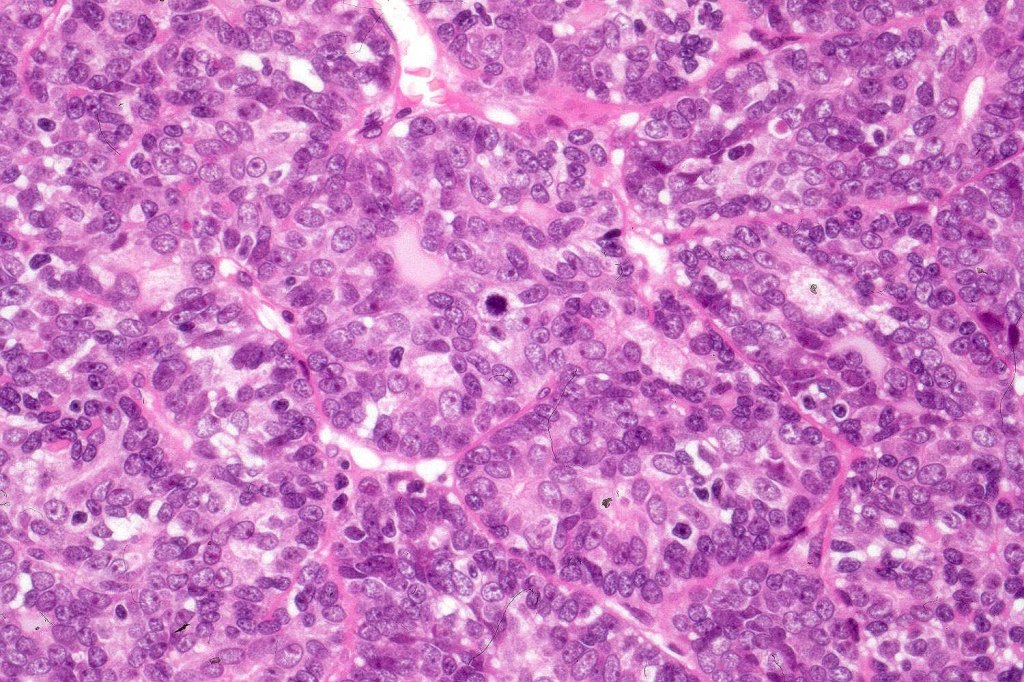

Histological features

•Malignant component shows loss of dual cell population, increased mitotic activity, atypical mitoses & necrosis

•Diagnosis depends on H/E rather than IHC

•The alternative classification into low grade (with only mild atypia and increased mitotic activity) and high grade variants has some merit although in any individual case this can be hard to apply unless the whole tumor has been sampled and is of uncertain biological merit.